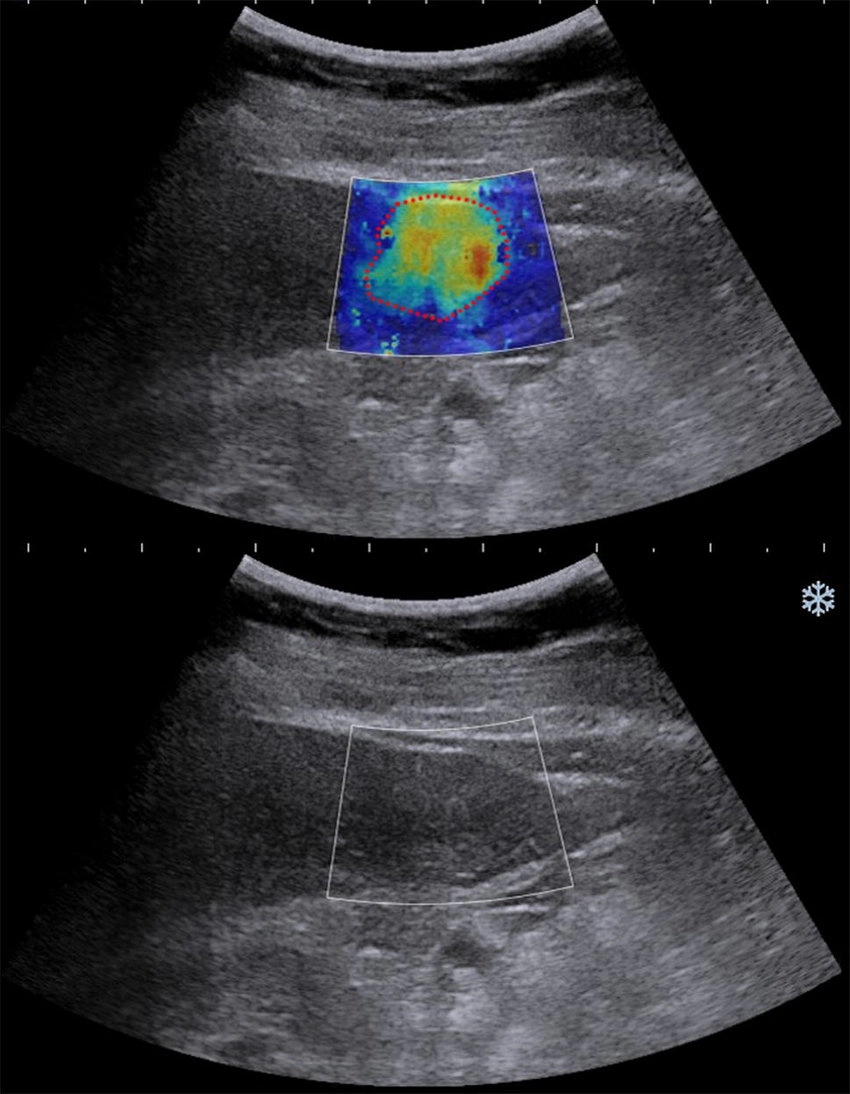

- B型肝炎以及C型肝炎因為慢性的發炎讓患者的肝臟逐步的纖維化但因為沒有任何的癥狀所以患者以及醫師便無法了解患者本身纖維化的程度甚至硬化的程度。肝炎帶原者若合併肝臟纖維化發生肝癌以及併發證的機率會顯著的上升。不論是超音波、核磁共振、或電腦斷層都無法正確判斷肝臟纖維化的程度,往往需要患者住院做肝切片的檢查才有辦法做較為正確的診斷。ARFI超音波的發明讓患者不要再做切片就能做診斷。經過國際醫學會證實ARFI超音波尤其是2D shear wave技術在各個方面對肝纖維化硬化的診斷都超過核磁共振以及電腦斷層。

- 脂肪肝是個常見的疾病也是讓患者以及醫師會忽略的疾病。近幾年來醫學界發現脂肪肝若有發炎或者合併肝纖維化容易在中老年時期有心血管疾病、心肌梗塞、腦中風、腎臟衰竭、肝硬化併發症、以及其他器官的癌症的發生。在美國有1/3因脂肪肝併發癌症,同時也是美國肝臟移植的主要原因。美國國際醫學會以及歐洲醫學會的數據顯示ATI超音波技術對脂肪肝的分層診斷精確度已經超過昂貴的核磁共振以及電腦斷層。本院於2024年9月率先引進ATI超音波脂肪肝診斷技術讓患者不用再住院切片即能精確診斷脂肪肝的嚴重程度。讓患者可以積極的介入治療,避免中老年時期脂肪肝合併症的發生。